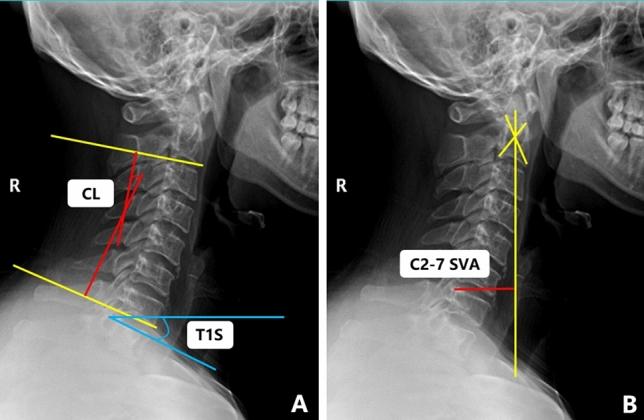

To explore the favorable factors that help slow the progression of disease in patients with mild Cervical Spondylotic Myelopathy (CSM). A retrospective analysis was conducted, involving the enrollment of 115 CSM patients. The categorization of patients into two groups was based on the duration of symptoms, assessments using the mJOA scale and Health Transition (HT) scores: mild-slow group and severe-rapid group. We found that the patients in both groups had similar degrees of spinal cord compression, but mild-slow group were older and had smaller C2-C7 cobb angle (Flexion) (CL(F)), C2-C7 cobb angle (Range of motion) (CL(ROM)), Transverse area (TA), Normal-TA, Compressive spinal canal area (CSCA), Normal-Spinal canal area (Normal-SCA) and lower Spinal cord increased signal intensity (ISI) Grade than the severe-rapid group. A binary logistic regression analysis showed that CL(ROM) and Normal-TA are favorable factors to help slow the progression of disease patients with mild CSM. Through ROC curves, we found that when CL(ROM) < 39.1° and Normal-TA < 80.5mm2, the progression of disease in CSM patients may be slower. Meanwhile, we obtained a prediction formula by introducing joint prediction factor: L = CL(ROM) + 2.175 * Normal-TA. And found that when L < 213.0, the disease progression of patients may be slower which was superior to calculate CL(ROM) and Normal-TA separately.

为了探索有助于减缓轻度颈椎病性脊髓病(CSM)患者疾病进展的有利因素。进行了回顾性分析,共纳入 115 例 CSM 患者。根据症状持续时间、mJOA 量表和健康转移(HT)评分将患者分为两组:轻度-缓慢组和严重-快速组。我们发现两组患者脊髓受压程度相似,但轻度-缓慢组年龄较大,C2-C7 Cobb 角(屈伸)(CL(F))、C2-C7 Cobb 角(活动范围)(CL(ROM))、横截面积(TA)、正常-TA、压缩椎管面积(CSCA)、正常椎管面积(Normal-SCA)和较低的脊髓高信号强度(ISI)分级较小。二项逻辑回归分析表明,CL(ROM)和 Normal-TA 是有助于减缓轻度 CSM 患者疾病进展的有利因素。通过 ROC 曲线,我们发现当 CL(ROM) < 39.1°和 Normal-TA < 80.5mm2 时,CSM 患者的疾病进展可能较慢。同时,我们通过引入联合预测因子获得了一个预测公式:L = CL(ROM) + 2.175 * Normal-TA。并发现当 L < 213.0 时,患者的疾病进展可能较慢,优于单独计算 CL(ROM)和 Normal-TA。